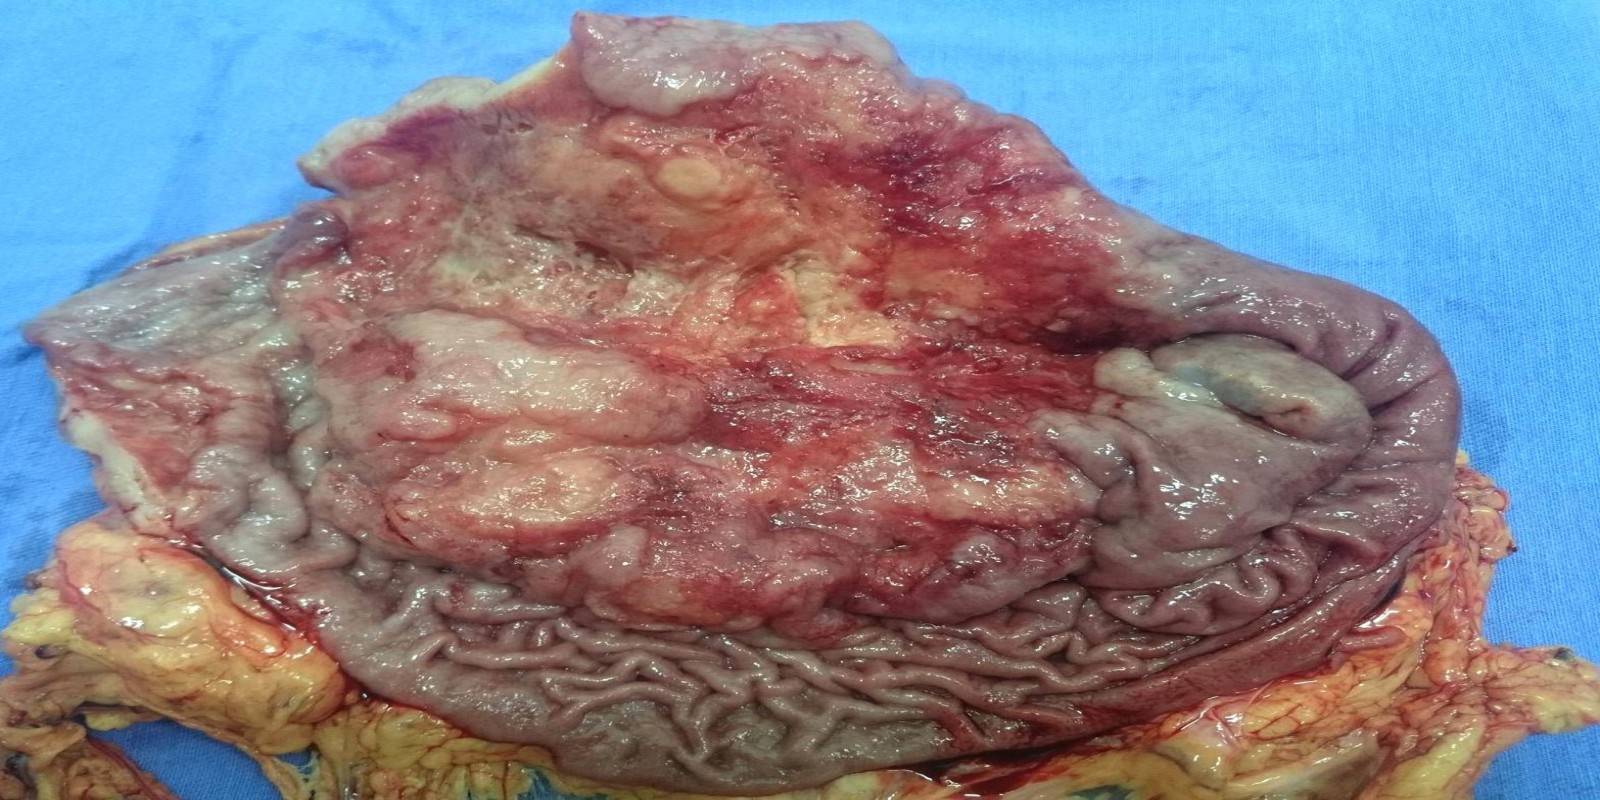

Câncer Gástrico

Gastric cancer